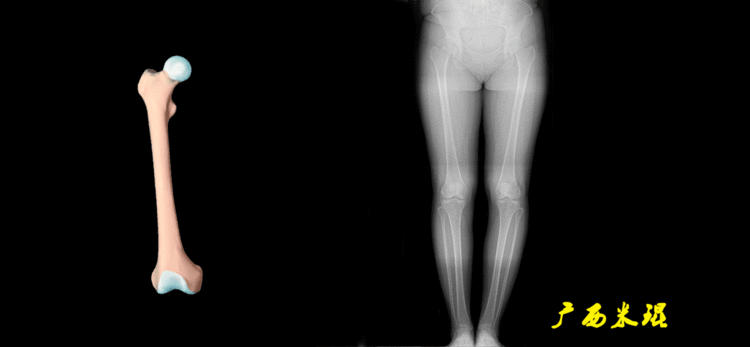

下肢力线及相关角度测量的前提是必须拍摄标准的站立位也就是负重位的下肢全长片。目前这样的照片都是放射科的技师在电脑上拼接出来的,大部分医院的DR都能够做到这一点。

无论如何,拍摄出来的下肢全长片必须包含髋关节中心、膝关节中心及踝关节中心,否则对临床是无用的。有了一张下肢的全长照片,我们需要确定下肢关节的中心点,通过中心点画出下肢的各种轴线,然后利用轴线与关节线的相交得出各种所需要的角度。

1、确定下肢关节的中心点(1)髋关节中心髋关节中心点由股骨头来确定,由于股骨头是相对比较规则的圆形,使用Mose圈或圆规就能确定股骨头中心也就是髋关节中心。

(2)膝关节中心膝关节中心点常用的有5个不同的定位方法,分别是股骨髁中点、股骨髁间窝顶点、膝关节间隙水平软组织中点、胫骨髁间嵴中点和胫骨平台中点,我们可以根据具体情况来选用。

(3)踝关节中心踝关节中心点常用的也有3个,分别是骨骼(内、外踝表面间距)中点、踝关节间隙水平软组织中点和距骨宽度中点。